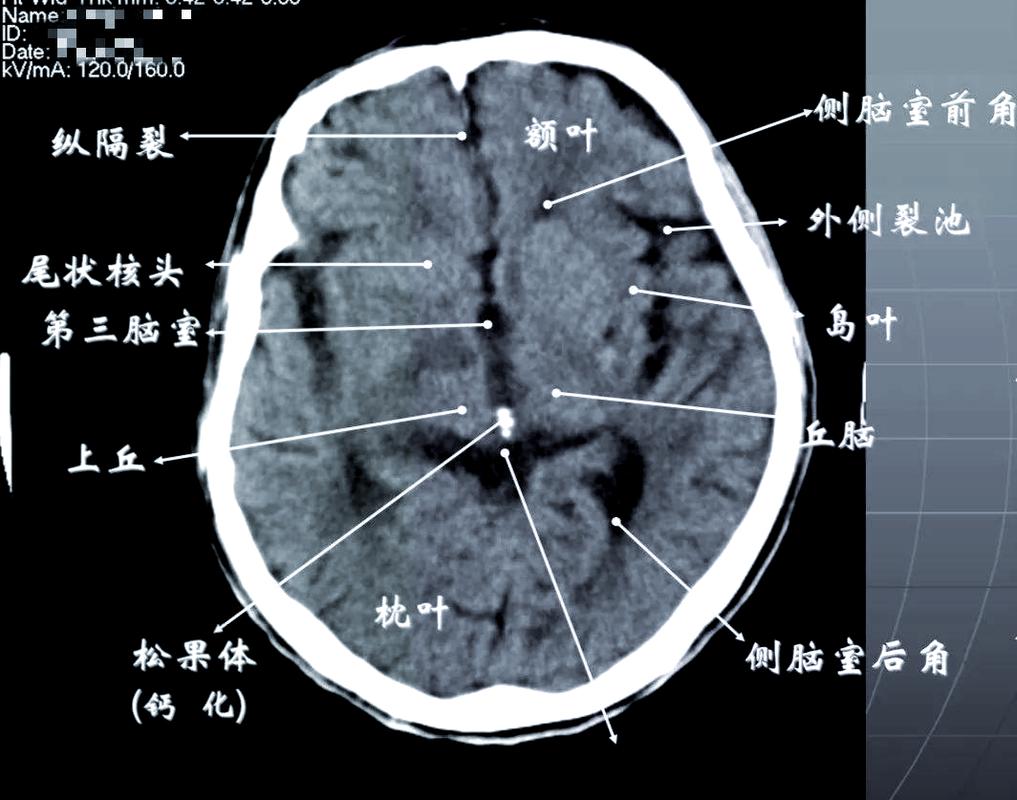

基础篇:脑CT报告单上,这些“名词”你必须知道

在看图之前,我们首先要了解CT报告单上常见的“黑话”,一张标准的脑CT报告单通常包含以下几部分:

- 检查描述 (Imaging Findings): 这是核心部分,描述了CT图像上观察到的具体情况。

- 印象 (Impression/Conclusion): 这是医生根据图像给出的初步判断,脑梗死可能”、“未见明显异常”等。

核心术语解读:

- 密度: 这是CT影像的灵魂,人体不同组织的密度不同,在CT上显示的颜色也不同。

- 高密度: 骨骼、钙化、新鲜出血等,在CT图像上呈现白色。

- 等密度: 与脑灰质密度相近,不易分辨。

- 低密度: 水肿、炎症、梗死、陈旧性病变等,在CT图像上呈现黑色或灰色。

- 脑沟、脑裂、脑池: 大脑表面的沟壑和腔隙,里面充满脑脊液(密度低,呈黑色),正常情况下,这些结构清晰。

- 脑室: 内含脑脊液的腔隙,如侧脑室、第三脑室、第四脑室,正常时对称,大小适中。

- 中线结构: 指大脑正中的结构,如透明隔、第三脑室、脑干等,正常时居中。

- 病灶: 指影像上看到的异常区域,对于脑梗,我们关注的是“低密度灶”。